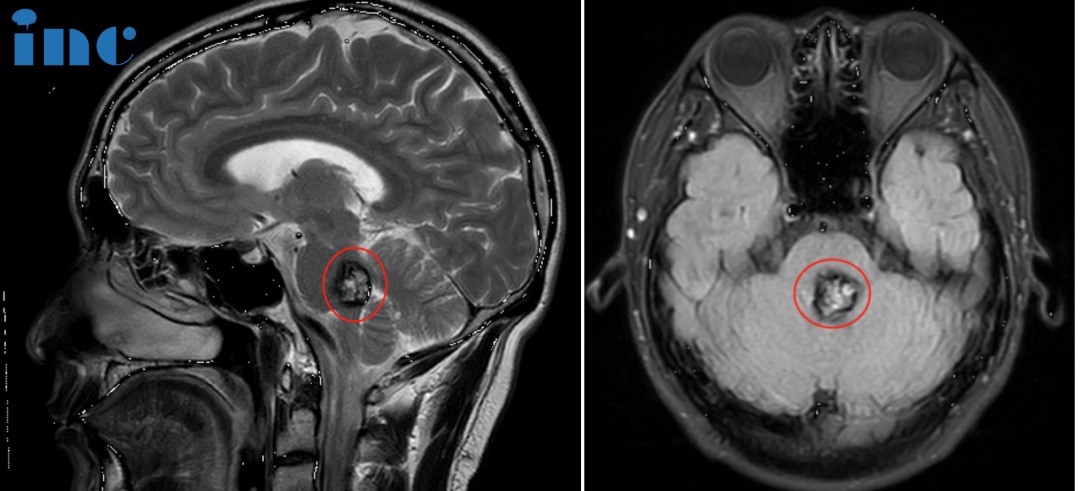

▼脑干海绵状血管瘤术前MRI